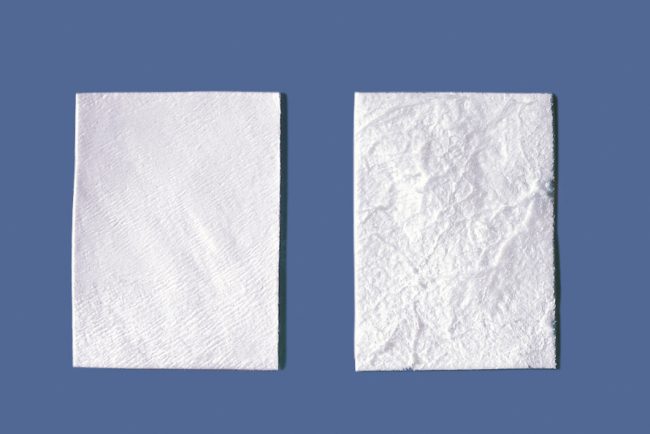

— барьерные мембраны, коллагеновые и не очень:

Барьерные мембраны

Не акцентируя внимания на производителях и материалах, все существующие барьерные мембраны можно разделить на две большие группы: резорбируемые и не резорбируемые. В последнее время появились еще т. н. «полурезорбируемые» мембраны, т. е. с длинным сроком резорбции, но один фиг — они всё равно рано или поздно резорбируются так, что являются резорбируемыми.

Вопреки распространенному мнению, именно барьерные мембраны являются самым главным расходником при остеопластике. Потому, что используются не только при НКР:

Итак, первая функция барьерной мембраны — это изоляция:

Барьерная мембрана может играть две роли, изолирующую и контурирующую.

В случае, если контур будущего альвеолярного отростка задается какими-то другими элементами (блоком, пластиной, сеткой и т. д.), в фиксации большинства мембран нет необходимости

Если же барьерная мембрана сама по себе является каркасом (например, при НКР), то ее обязательно нужно фиксировать любым доступным способом.